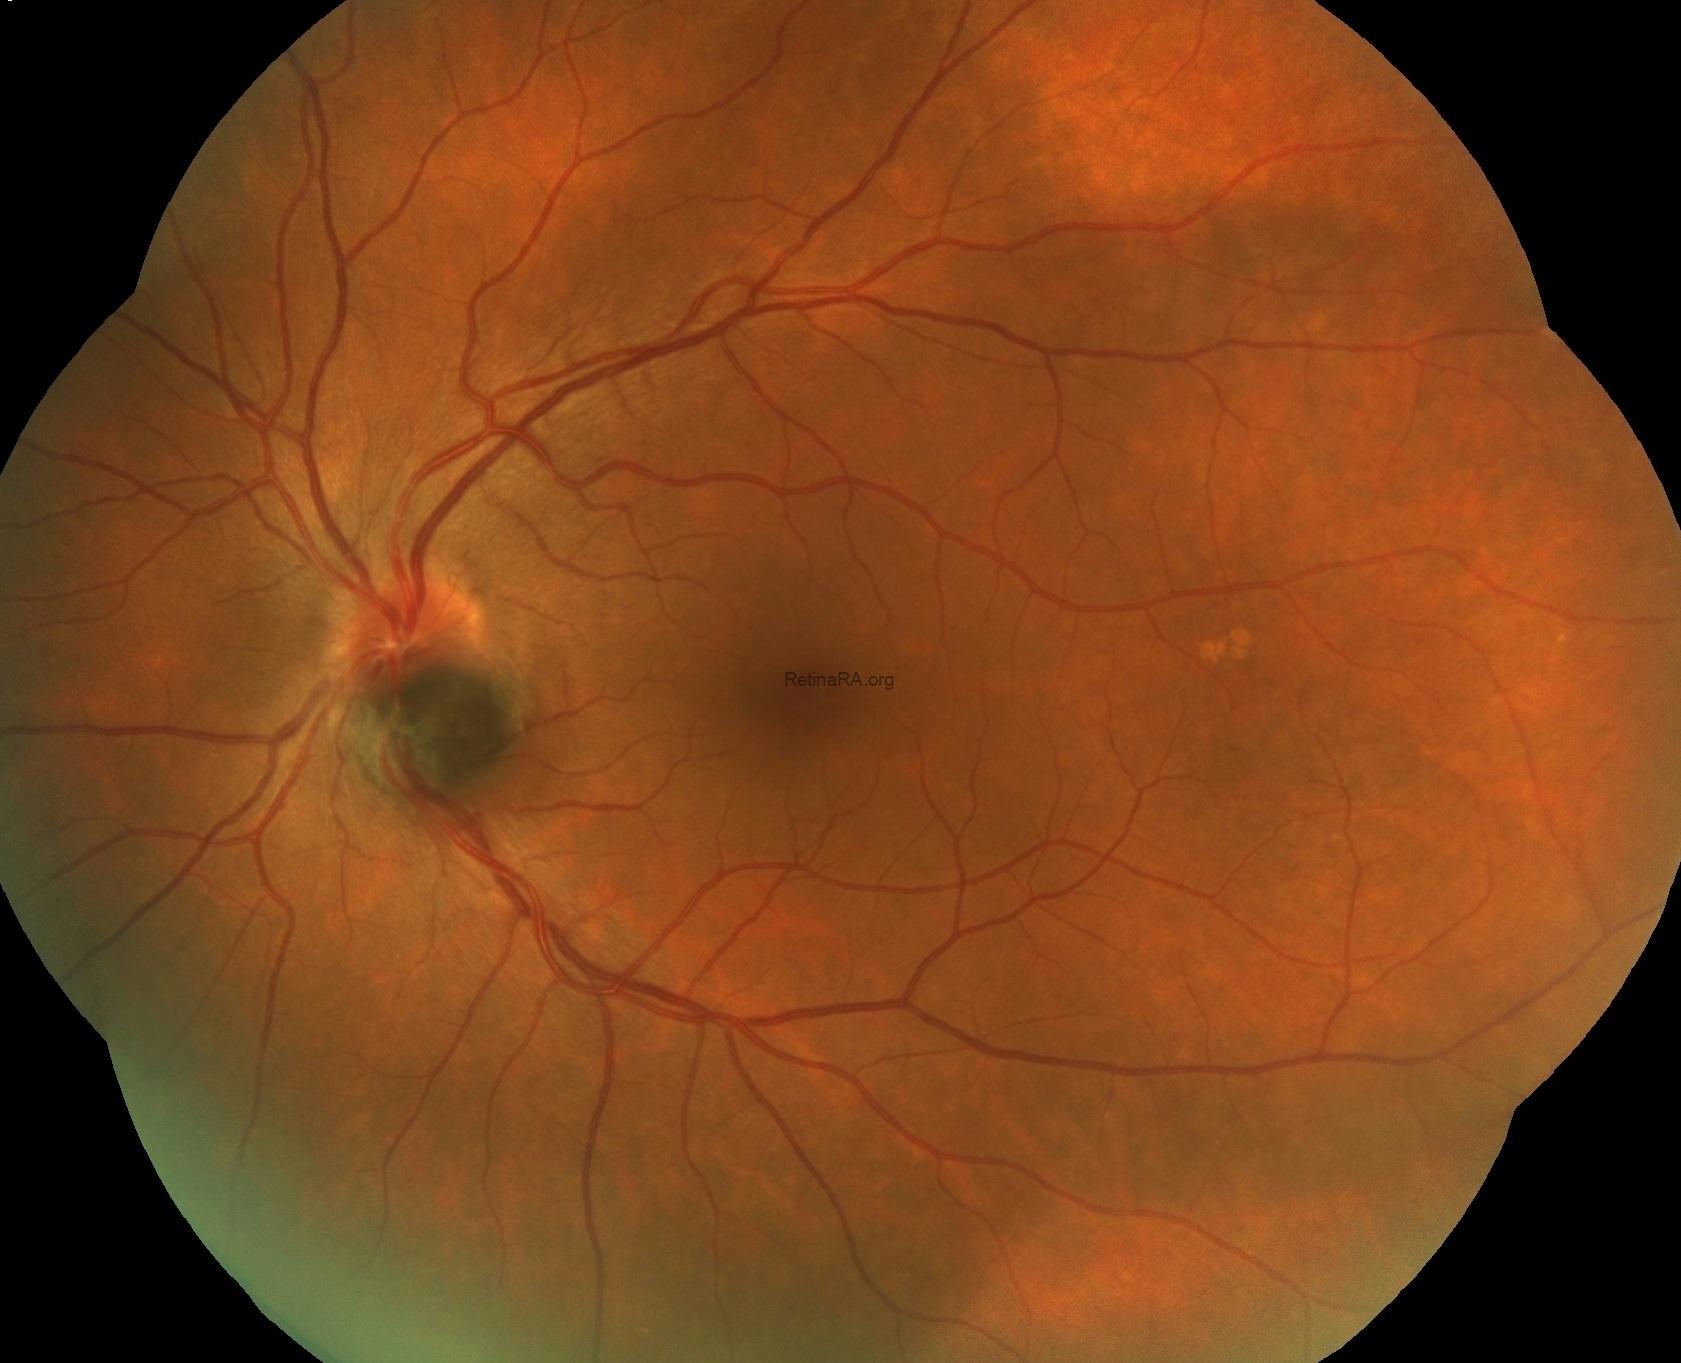

While the fundus examination of the right eye was completely normal; the left eye showed well-defined gray-black pigmentation at the inferior margin of the optic disc extending to the inferiortemporal retina. The lesion was elevated with feathery margins about 1.0 disc-area in size with the involvement of adjacent choroid. Lipofuscin deposition, retinal hemorrhages, retinal edema and subretinal fluid were absent. There were not any other retinal lesions or ocular melanocytosis. The vitreous was clear. Pupillary light reflexes were brisk and equal bilaterally.

Fundus fluorescein angiography revealed hypo-fluorescence of the mass lesion in all stages without any evidence of late phase hyper-fluorescence. There was staining of the disc margins superiorly.

Fundus autofluoresce demonstrated hypo-autofluorescence corresponding to the pigmented mass on the optic disk.